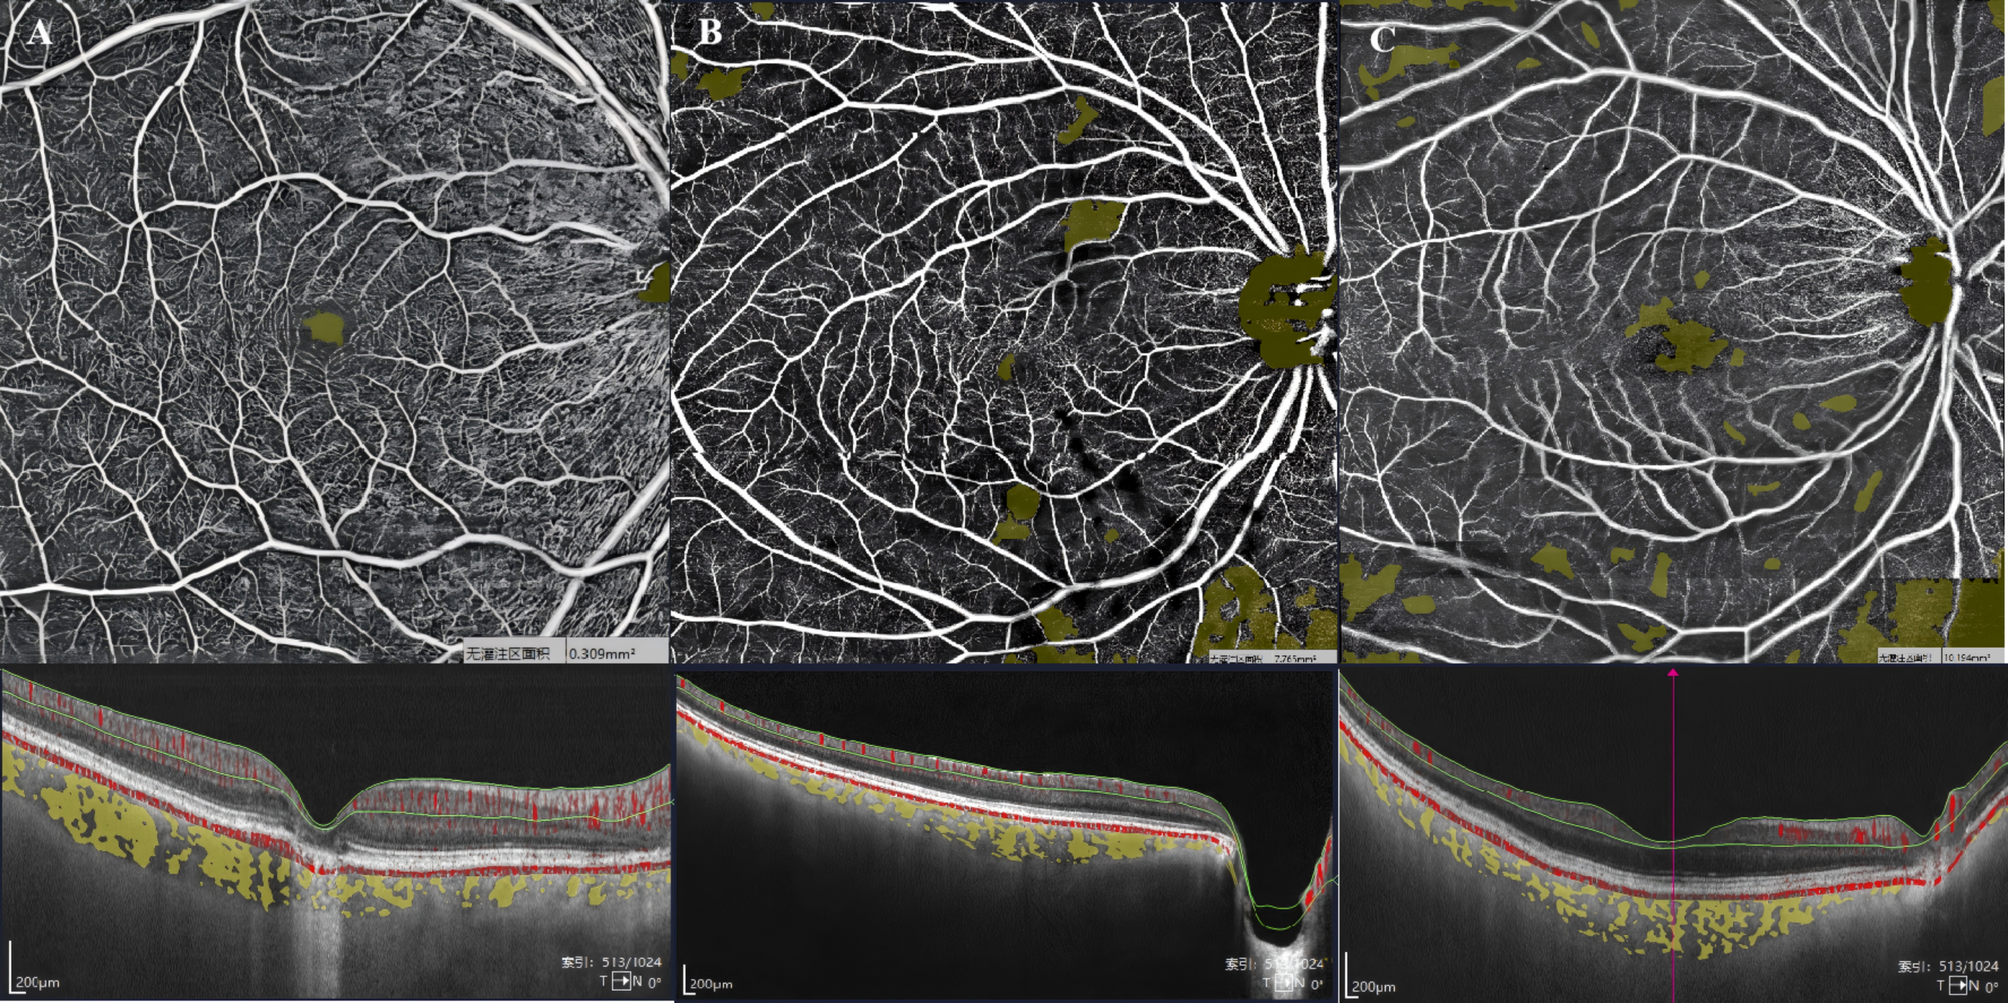

Fig. 4

Representative images illustrating macular retinal SVD in three subjects: one healthy control and two CPACG patients with different disease severities. The upper panels show OCTA images, where yellow areas indicate non-perfusion regions. The lower panels show the corresponding OCT B-scans, with the retinal SVC defined as the area between the two green segmentation lines. (A) A 63-year-old healthy female without visual field defects, showing a dense capillary network with minimal non-perfusion areas and high vascular density. (B) A 59-year-old female with CPACG (mean deviation = − 10.45 dB), showing a moderately dense capillary network, medium-sized non-perfusion areas, and moderate vascular density. (C) A 64-year-old female with CPACG (mean deviation = − 17.62 dB), showing a sparse capillary network, extensive non-perfusion areas, and reduced vascular density.